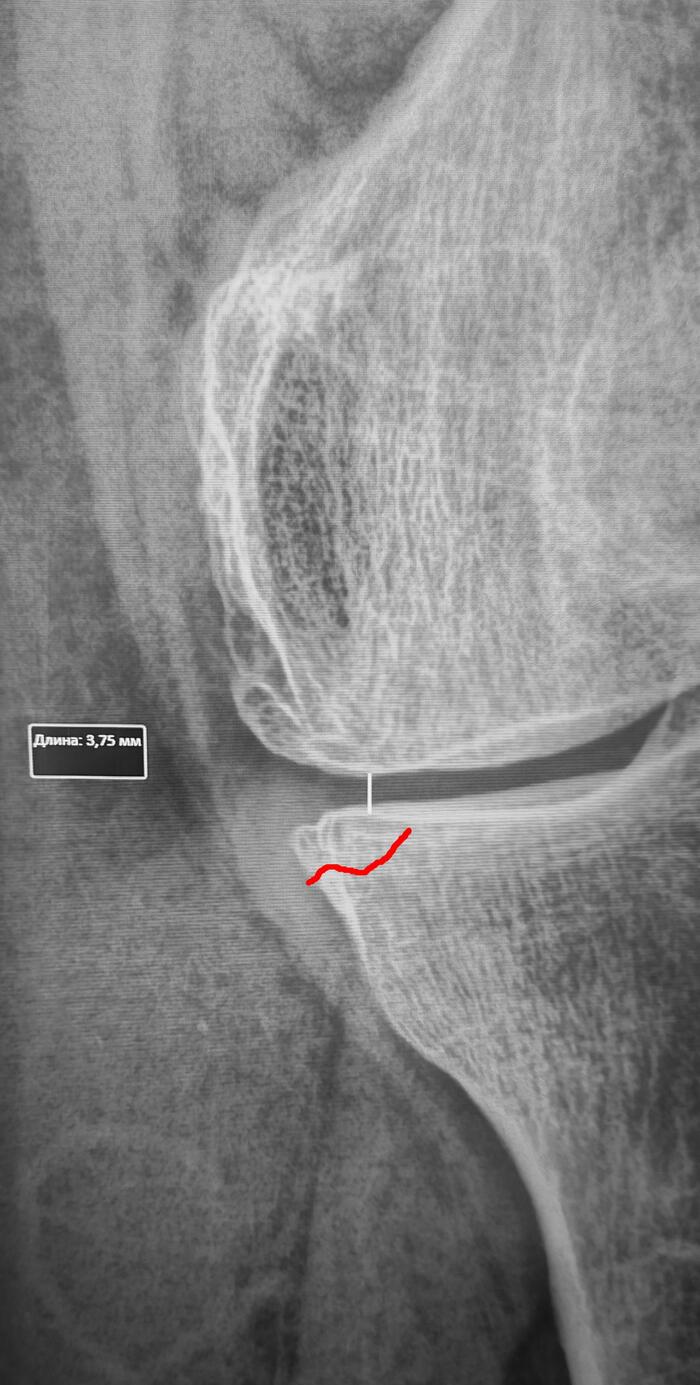

Рентген (на ранних стадиях может не показать перелом)

Косая линия просветления костной ткани в медиальном мыщелке левой б/б кости, сужение рентгенологической щели левого коленного сустава в медиальных отделах до 3.7,краевые остеофиты, субхондральный склероз суставной поверхности, заострение, деформация межмыщелковых возвышений. Заключение: Стресс-перелом медиального мыщелка левой большеберцовой. Гонартроз слева 2 ст.

Категория годности по ст.85(Временные функциональные расстройства костно-мышечной системы, соединительной ткани, кожи и подкожной клетчатки после лечения болезней, ранений, травм, отравлений и других воздействий внешних факторов) Г-временно не годен к военной службе сроком на 3 мес., с последующим оформление с диагнозом гонартроз 2 ст. по ст.65в-В(ограниченно годен к в/сл).